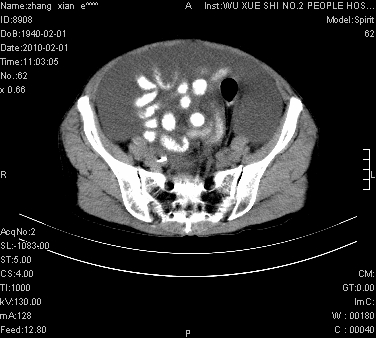

大量腹水,脾脏囊性占位,子宫颈占位,右侧腹股沟淋巴结肿大,建议+c,先查妇科。

腹盆腔大量积液,子宫增大,子宫颈增大外形不规则,内见低密度影,膀胱后壁显示不清,右腹股沟肿大淋巴结,脾脏囊性占位,子宫颈占位,子宫颈癌?建议增强。

考虑:1、腹膜转移,大量腹水;

2、脾占位性病变;

3、左侧卵巢占位性病变,建议增强进一步检查。

腹盆腔大量积液,子宫增大,子宫颈增大外形不规则,内见低密度影,膀胱后壁显示不清,右腹股沟肿大淋巴结,脾脏囊性占位,子宫颈占位,子宫颈癌?建议增强。支持!

考虑:1、腹膜转移,大量腹水;2、脾占位性病变;3、左侧卵巢占位性病变,建议增强进一步检查。支持